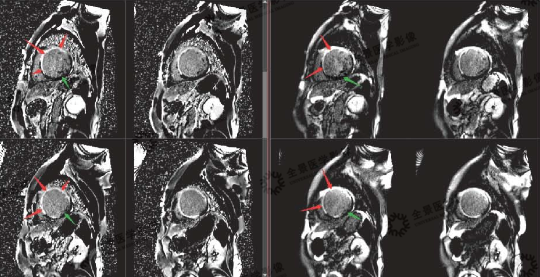

▲延迟强化序列:

红色箭头:梗死心肌

绿色箭头:正常心肌